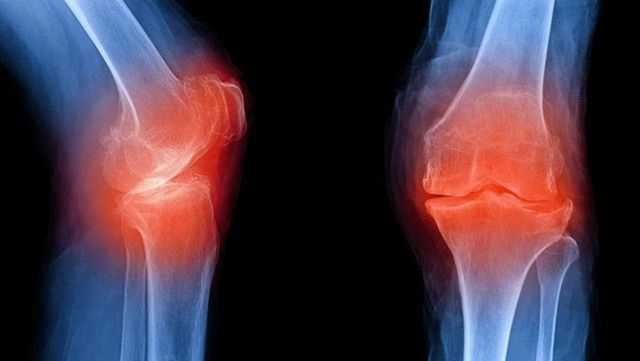

Thoái hóa khớp là loại viêm khớp phổ biến nhất với hàng trăm triệu người mắc phải trên toàn thế giới. Thoái hóa khớp xảy ra khi sụn bị hao mòn hoặc phá hủy. Sụn là mô liên kết bao bọc các đầu xương, giúp cho khớp chuyển động trơn tru và giảm lực tác động lên các xương.

Triệu chứng ban đầu thường gặp của bệnh thoái hóa khớp là đau khớp. Các triệu chứng khác còn có cứng khớp, khớp phát ra âm thanh bất thường hoặc khó chịu tại một thời điểm nhất định vào ban ngày hoặc ban đêm.